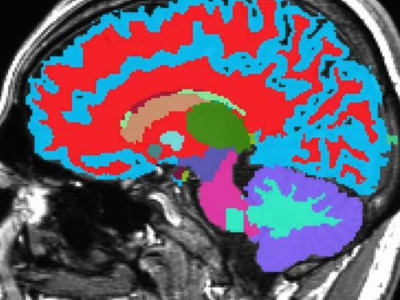

Inggris Raya, Britania Raya - UK Biobank telah melakukan proyek pencitraan tubuh manusia terbesar di dunia dengan melibatkan 100.000 sukarelawan selama 15 tahun. Data ini mencakup gambar otak, jantung, abdomen, pembuluh darah, tulang, dan sendi dari para peserta.

Dengan investasi £60 juta dan teknologi canggih, para peneliti mengumpulkan ribuan gambar MRI dan ultrasonografi untuk mendapatkan gambaran detail tentang tubuh manusia. Data ini membantu mempelajari ukuran, bentuk, dan komposisi organ dan jaringan dalam waktu sangat singkat.

Data dari UK Biobank sangat lengkap karena juga menggabungkan informasi gaya hidup, genetika, dan hasil kesehatan para sukarelawan. Hingga saat ini, lebih dari 1.300 penelitian ilmiah telah menggunakan data ini untuk mengembangkan diagnosa dan pengobatan baru.